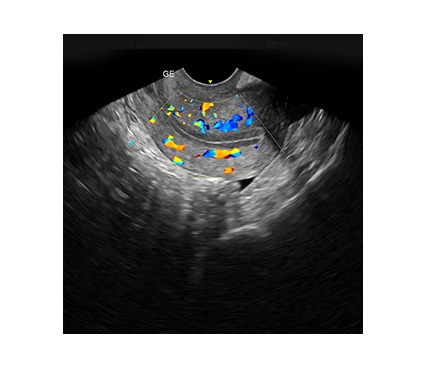

Our Women’s Health Fertility Scan offers a detailed pelvic examination, specifically designed for those who may be struggling to conceive or are about to start their fertility journey. This scan can be scheduled at various points during your cycle, and you may choose to attend up to three times during your menstrual cycle. The timing of your scans will be based on your individual cycle, so please consult your local clinic for more information on when to book.